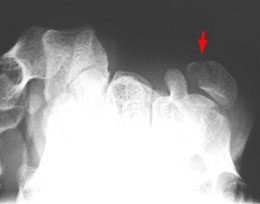

A - Radiographie, incidence oblique : Fracture du pisiforme.

B - Radiographie, incidence du canal carpien : Bonne visibilité de la fracture et du respect de l'apophyse de l'os crochu.

Fracture du pisiforme.